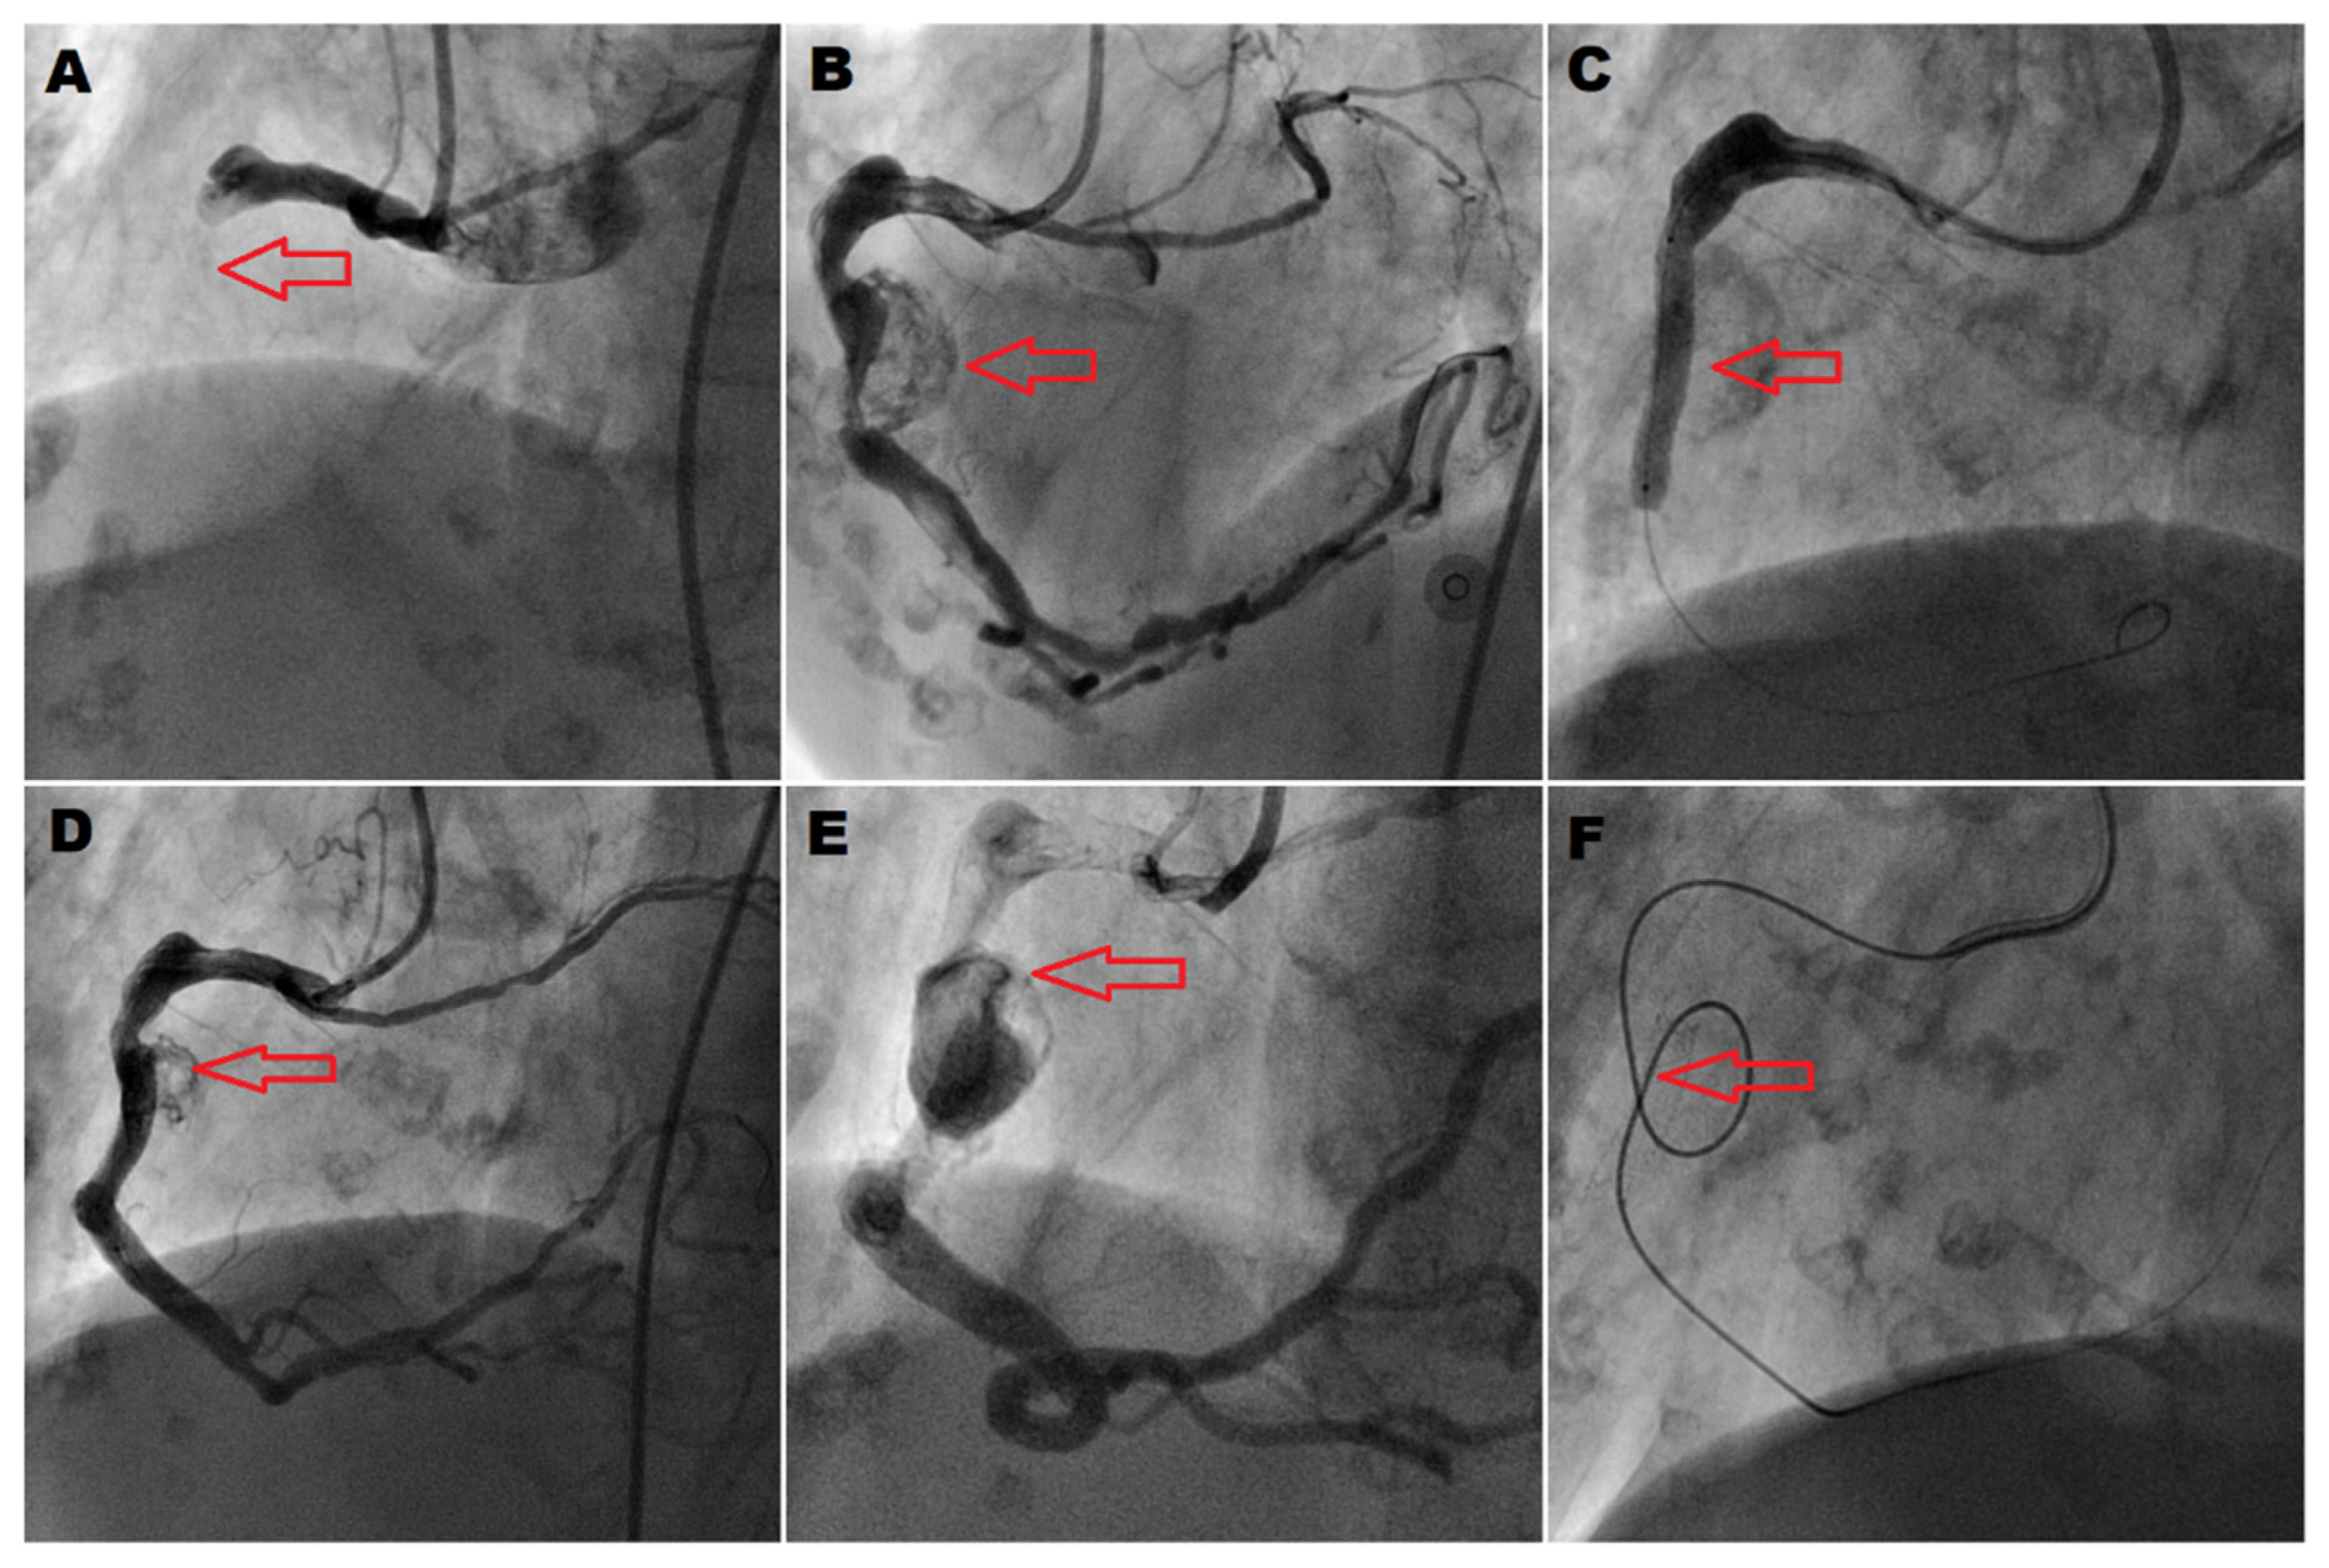

2. Case Presentation